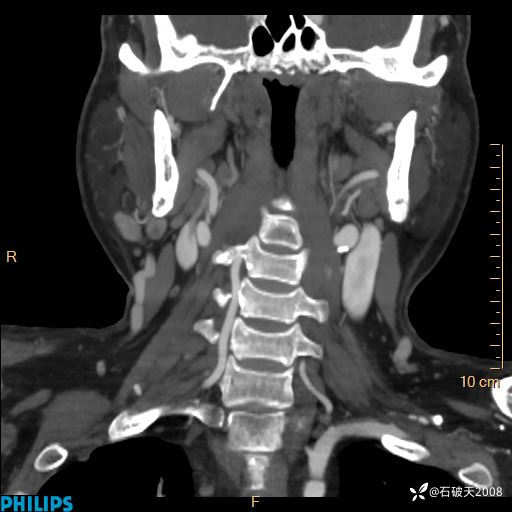

平扫